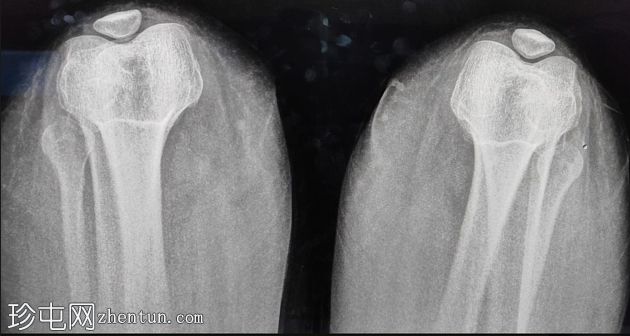

髌骨发育不全

X线片

髌骨相对于股骨滑车发育不良,但形状和结构正常。

其他方面正常。髌股关节间隙正常。未见骨折、碎裂、二分型或软骨损伤迹象。髌骨切线位片未见明显的滑车发育不良或倾斜。